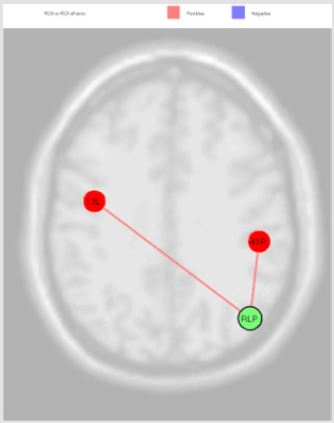

Figure 4: The connection of LLP source with Premotor Cortex (left) (beta -0.14; p=0.02), Dorsolateral Prefrontal Cortex (right) (beta -0.05; p=0.02) and Retrosplenial Cingulate Cortex (right) (beta -0.13; p=0.02), and with Primary Visual Cortex V1 (left) (beta 0.13; p=0.04).

The activation of LLP source, reported in the Figure 4, was inversely correlated with Premotor Cortex (left), Dorsolateral Prefrontal Cortex (right) and Retrosplenial Cingulate Cortex (right), and directly with Primary Visual Cortex V1 (left); the MPFC source was inversely correlated with Somatosensory Associative Cortex (right) and Anterior Entorhinal Cortex (right); the PCC source was directly correlated Anterior Cingulate Cortex (right), Anterior Cingulate Cortex (left), Subcentral Area (right), Somatosensory Associative Cortex (left) and Dorsal Anterior Cingulate Cortex (right); RLP source was directly correlated with Auditory Cortex (right) and Insula Cortex (left) Figure 5. Finally, we report the MPFC connections revealed in our experiments Figure 6.